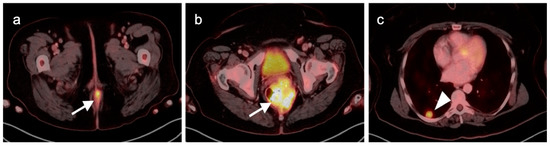

3. Gastrointestinal Stromal Tumor (GIST)